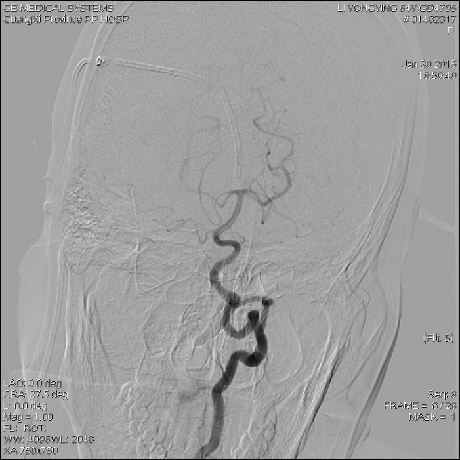

2015-1-30 DSA